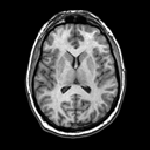

| The effect of a stereotactic radiosurgery

on a brain tumor Left: before surgery. Right: 4 months after surgery |